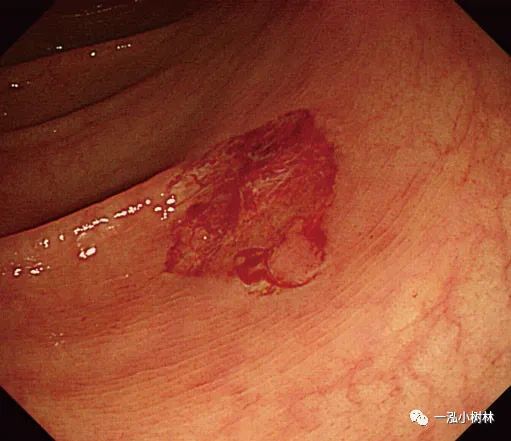

图1b 冷钳息肉摘除术后黏膜出血

图1c 小息肉切除瘢痕,5年后腺瘤复发